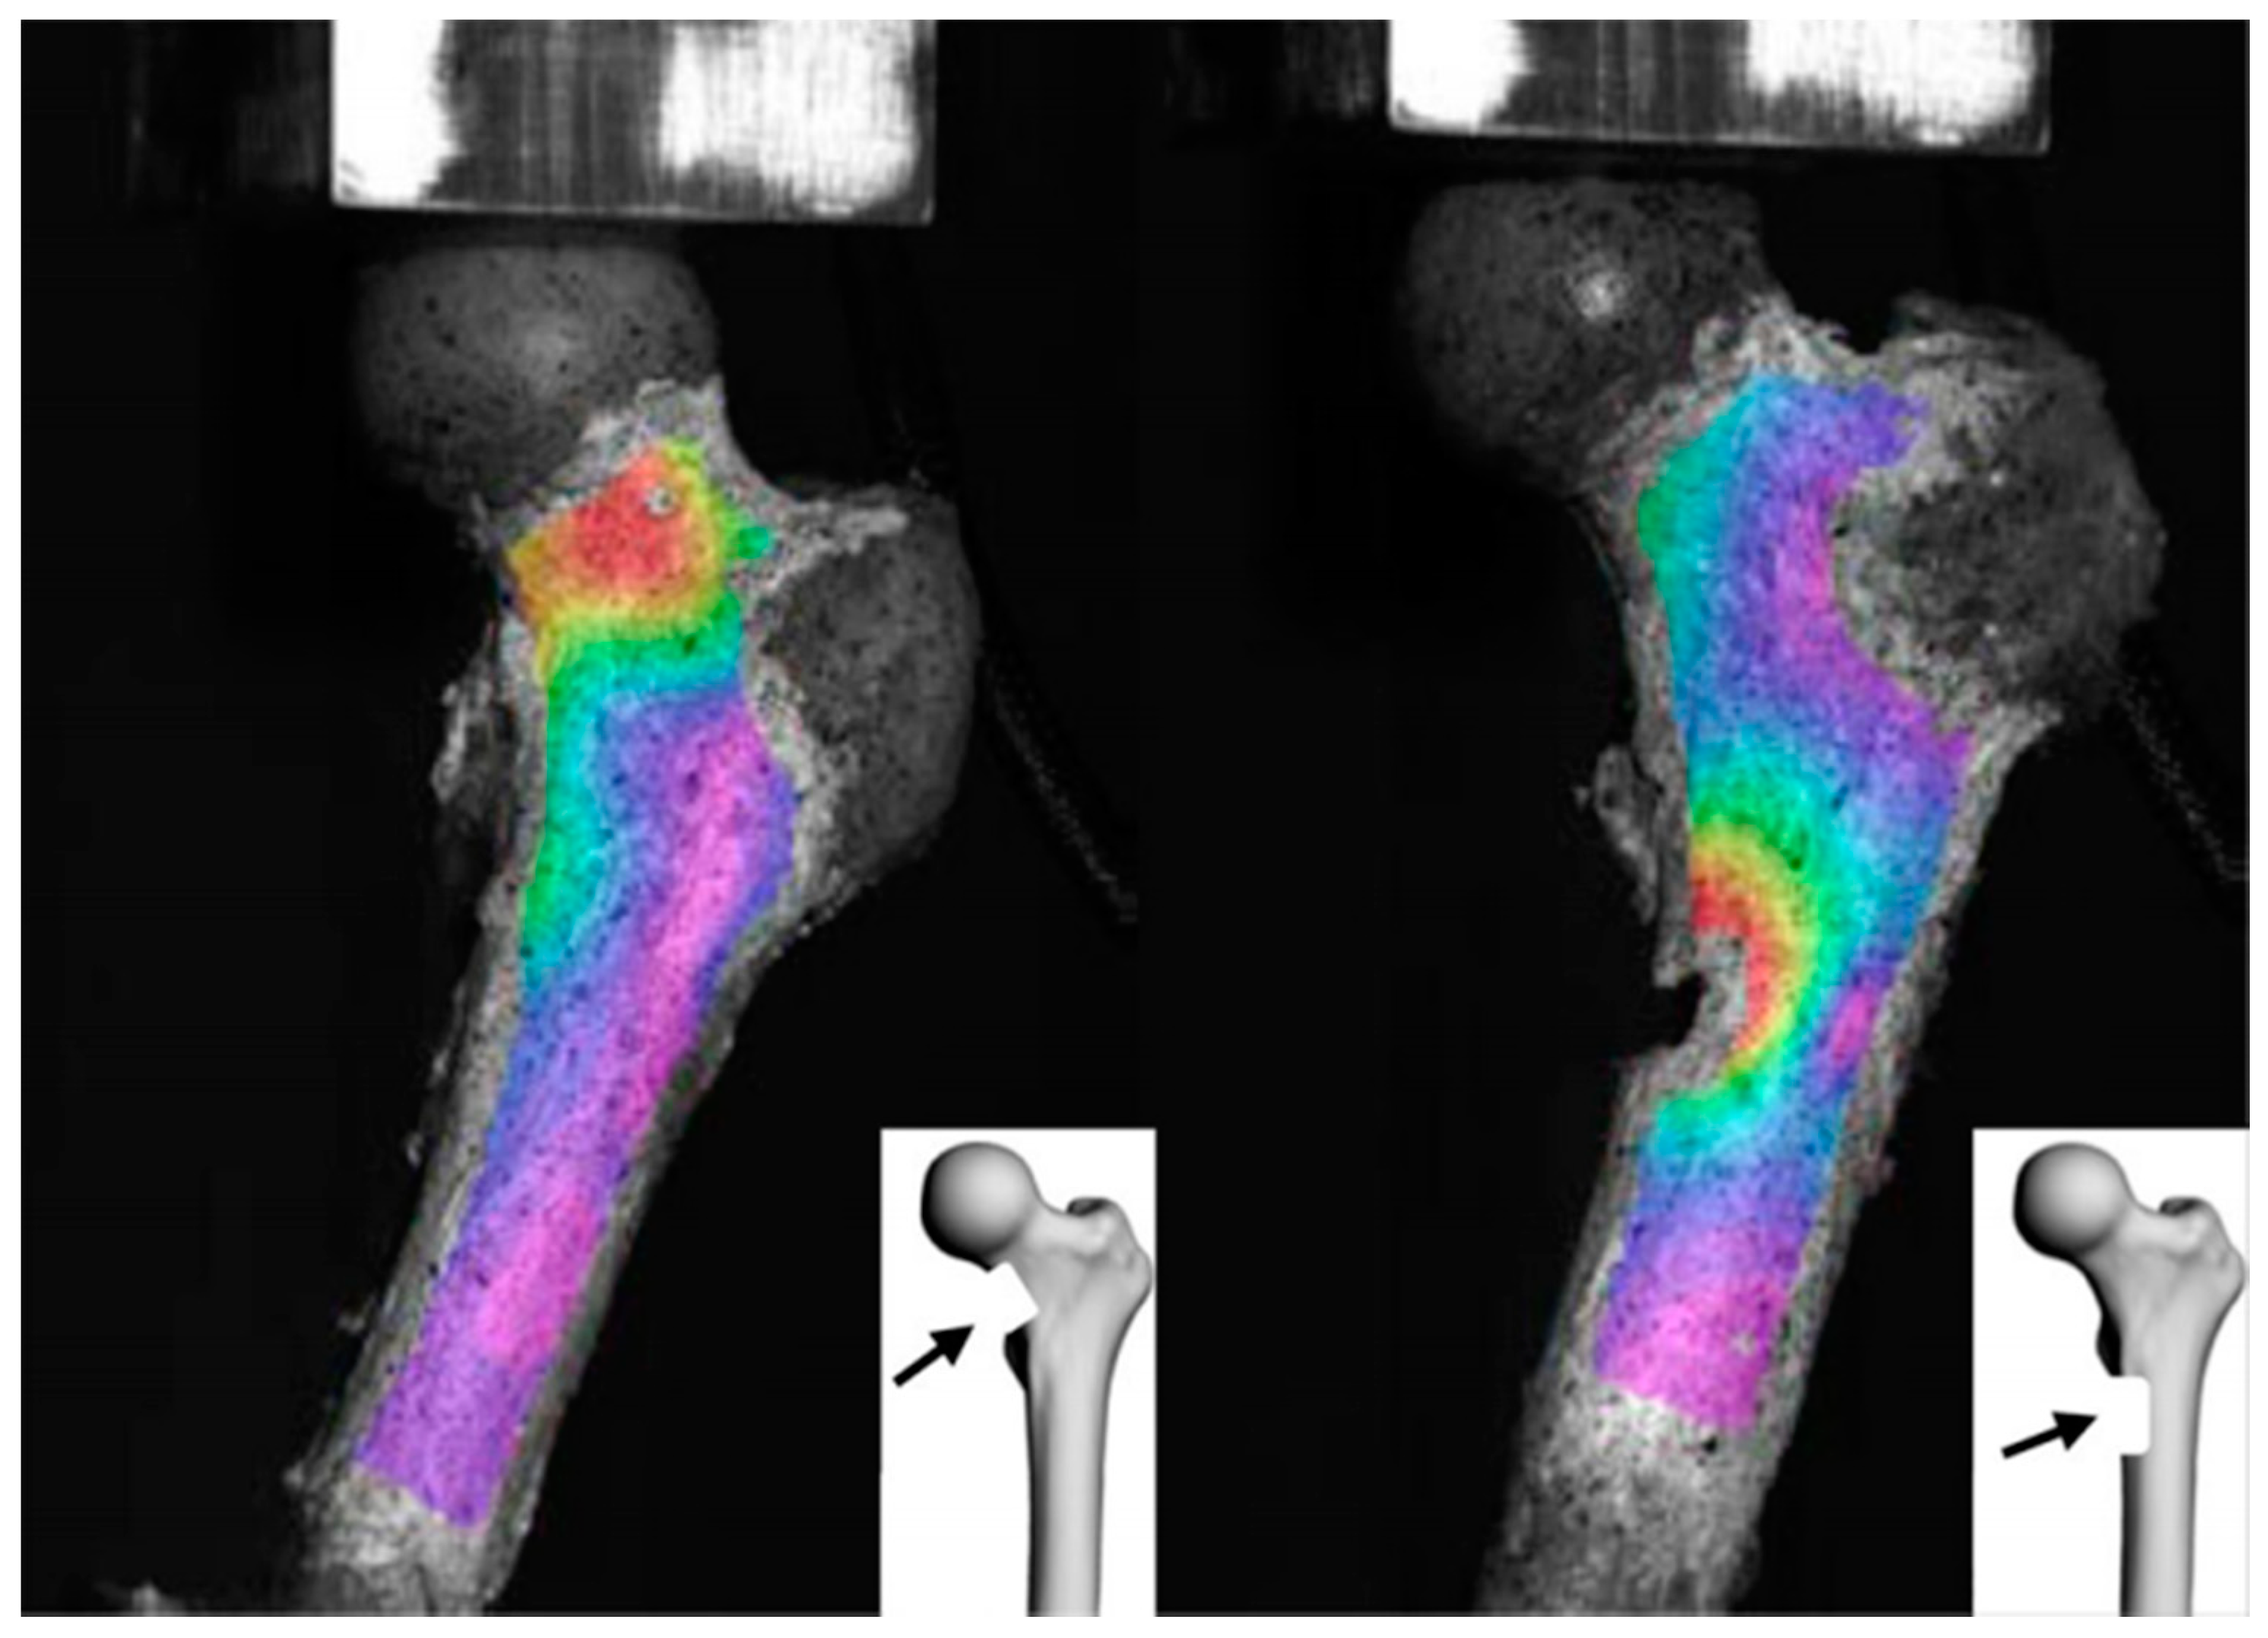

3.2. Computed Tomography–Finite Element Analysis (CT-FEA)

3.2.1. A Three-Dimensional Structural Modeling—Ex Vivo Studies

3.2.2. Towards New Threshold Criteria: Strain Fold Ratio and Failure Load